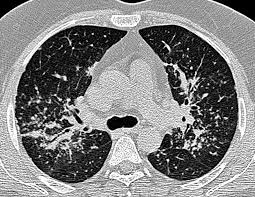

Sarcoidosis interstitial lung disease. Bilateral hilar adenopathy. When sarcoidosis causes scaring in the lungs it may be referred to as Interstitial Lung Disease ILD. Sarcoidosis a form of interstitial lung disease is a rare disease characterized by the discrete accumulation of inflammatory cells and matrix proteins granulomas in different parts of the body typically the lungs pulmonary sarcoidosis.

Interstitial lung disease is an umbrella term used to define a complex group of pulmonary diseases including sarcoidosis and idiopathic pulmonary fibrosis. Sarcoidosis is a rare disease caused by inflammation. Interstitial lung diseases ILDs result from damage to the alveoli air sacs leading to inflammation and fibrosis of the interstitium tissue wall between the.

Interstitial Lung Disease ILD and Sarcoidosis Program Interstitial Lung Disease ILD and Sarcoidosis Program. Sarcoidosis is a granulomatous disease of unknown cause occurs worldwide and has a highly variable prevalence. It causes small lumps of inflammatory cells in the lungs.

This disease is difficult to pin down in so many ways understanding if you have ILD as a result of sarcoidosis is just one of them. Sarcoidosis is a granulomatous disease of unknown cause occurs worldwide and has a highly variable prevalence. 1 Sarcoidosis affects only around 1-36 people in 100000 each year where 20 of these people develop ILD. At least 5 of cases include pulmonary arterial hypertension. 1 In this form of ILD scarring of the lung tissue might develop. Sarcoidosis is a rare disease caused by inflammation. It causes small lumps of inflammatory cells in the lungs. 1202 ILDdiffuse parenchymal lung diseases DPLD of known origin. The interstitial lung diseases ILDs are characterised by dyspnoea on exertion exercise-induced hypoxaemia reduced skeletal muscle function and exercise intolerance.

Sarcoidosis a form of interstitial lung disease is a rare disease characterized by the discrete accumulation of inflammatory cells and matrix proteins granulomas in different parts of the body typically the lungs pulmonary sarcoidosis. Overtime this can lead to permanent scarring or thickening of the organ tissue also called fibrosis. Sarcoidosis is a multisystem granulomatous disorder of unknown etiology that affects individuals worldwide and is characterized pathologically by the presence of noncaseating granulomas in involved organs. Interstitial lung disease ILD describes a broad category of. In this form of ILD scarring of the lung tissue might develop. Sarcoidosis affects only around 1-36 people in 100000 each year where 20 of these people develop ILD. Interstitial lung disease is an umbrella term used to define a complex group of pulmonary diseases including sarcoidosis and idiopathic pulmonary fibrosis.